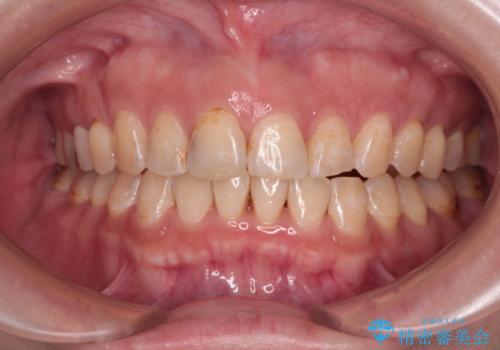

欠損した歯と前に飛び出した前歯 インプラント治療を併用したワイヤー矯正治療

- 上の前歯が下唇に当たる感覚と奥歯の欠損を気にして来院された患者様です。

上顎前歯の突出感は、上顎全体が前方に位置していることが原因であったため、補助装置により上顎全体を後方に移動させることとしました。

後方移動と同時上下歯列をワイヤー装置にて整え、奥歯の欠損部には矯正治療の途中でインプランを埋入していくこととしました。